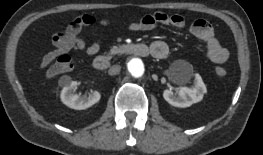

Мультиспиральная компьютерная томография является лучевым методом исследования и в режиме ангиографии применяется для диагностики сосудистой патологии брюшной аорты и ее ветвей. Сканирование проводится с помощью рентгеновских лучей, которые испускает трубка томографа, непрерывно вращаясь вокруг объекта исследования.

Особенностью КТ-ангиографии является обязательное применение контрастного усиления, которое позволяет визуализировать кровеносные сосуды. С помощью внутривенного введения йодсодержащих контрастных препаратов на снимках хорошо контрастируются висцеральные ветви и сама аорта, участки сужения и расширения сосудов, можно диагностировать атеросклеротические бляшки и тромбы в просвете сосудов.

При помощи цифровых приложений данные, полученные при сканировании, трансформируются в трехмерные изображения сосудистой системы. Это позволяет оценить пространственное соотношение анатомических структур и часто применяется в ходе предоперационной подготовки и для оценки успешности проведенной операции.